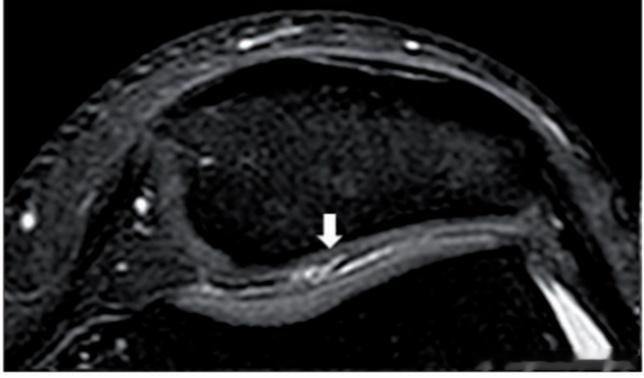

二级(图3):MRI显示关节软骨深度<50%,软骨层出现高信号的形态(裂缝、翻片、坑坑洼洼、软骨厚度丧失)

——症状:可能开始出现膝关节不适症状,活动中出现无力情况,但没有引起明显活动疼痛。